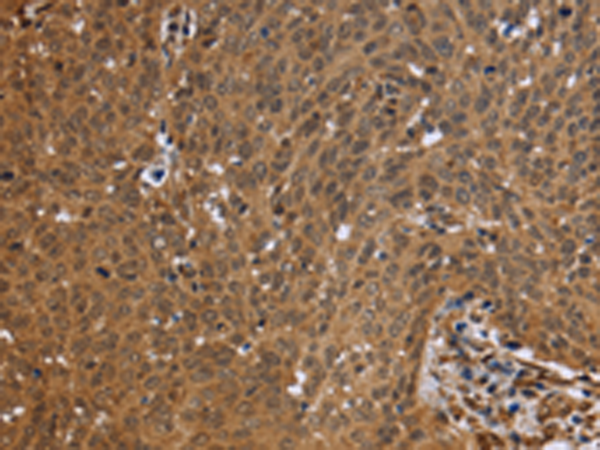

分类: 科研抗体货号: P08321别名:应用: IHC反应种属: Human, Mouse, Rat